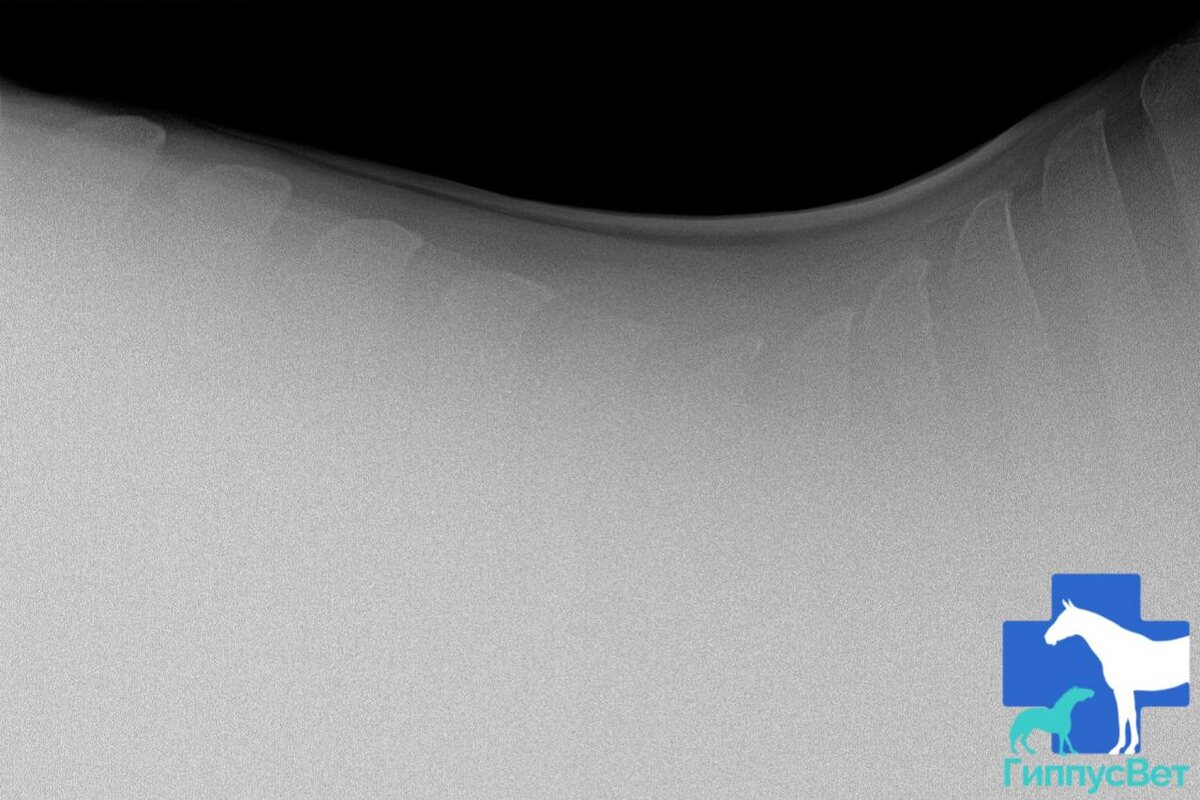

Фото из практики ветеринарной команды Гиппус Вет (телеграм hippusvet). Грудной отдел лошади, рентген.

Диагностика лордоза основана на клинических признаках. Рентгенография грудопоясничного отдела помогает определить, вызвана ли аномалия деформацией позвонков.